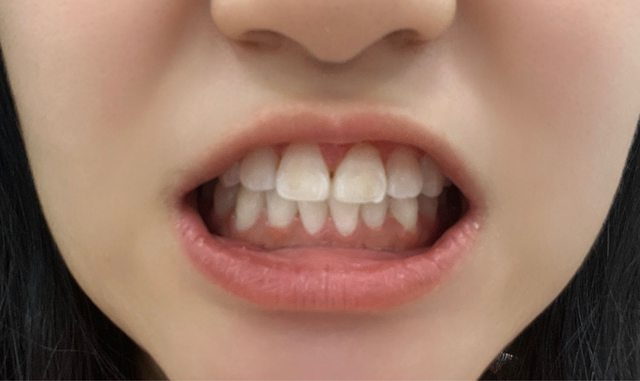

目前已經拔完三顆智齒, 本來想說等最後一顆水平的冒出頭再去拔, 結果現在不僅沒有冒出來連帶下排牙齒都擠到有點亂QQ 本來牙齒超級整齊,現在還要花錢去矯正下排 好後悔沒有早一點去全部拔掉, 但拔智齒真的好恐怖… 有人沒拔智齒牙齒還很整齊的嗎? 弱弱的附上看不出來很亂的牙齒 https://i.imgur.com/VVfXOlE.jpg

wendy113089 : 單看下排就很亂QQ101.10.9.126 10/06 15:46

wendy113089 : https://i.imgur.com/rvVnMjr.jpg101.10.9.126 10/06 15:46